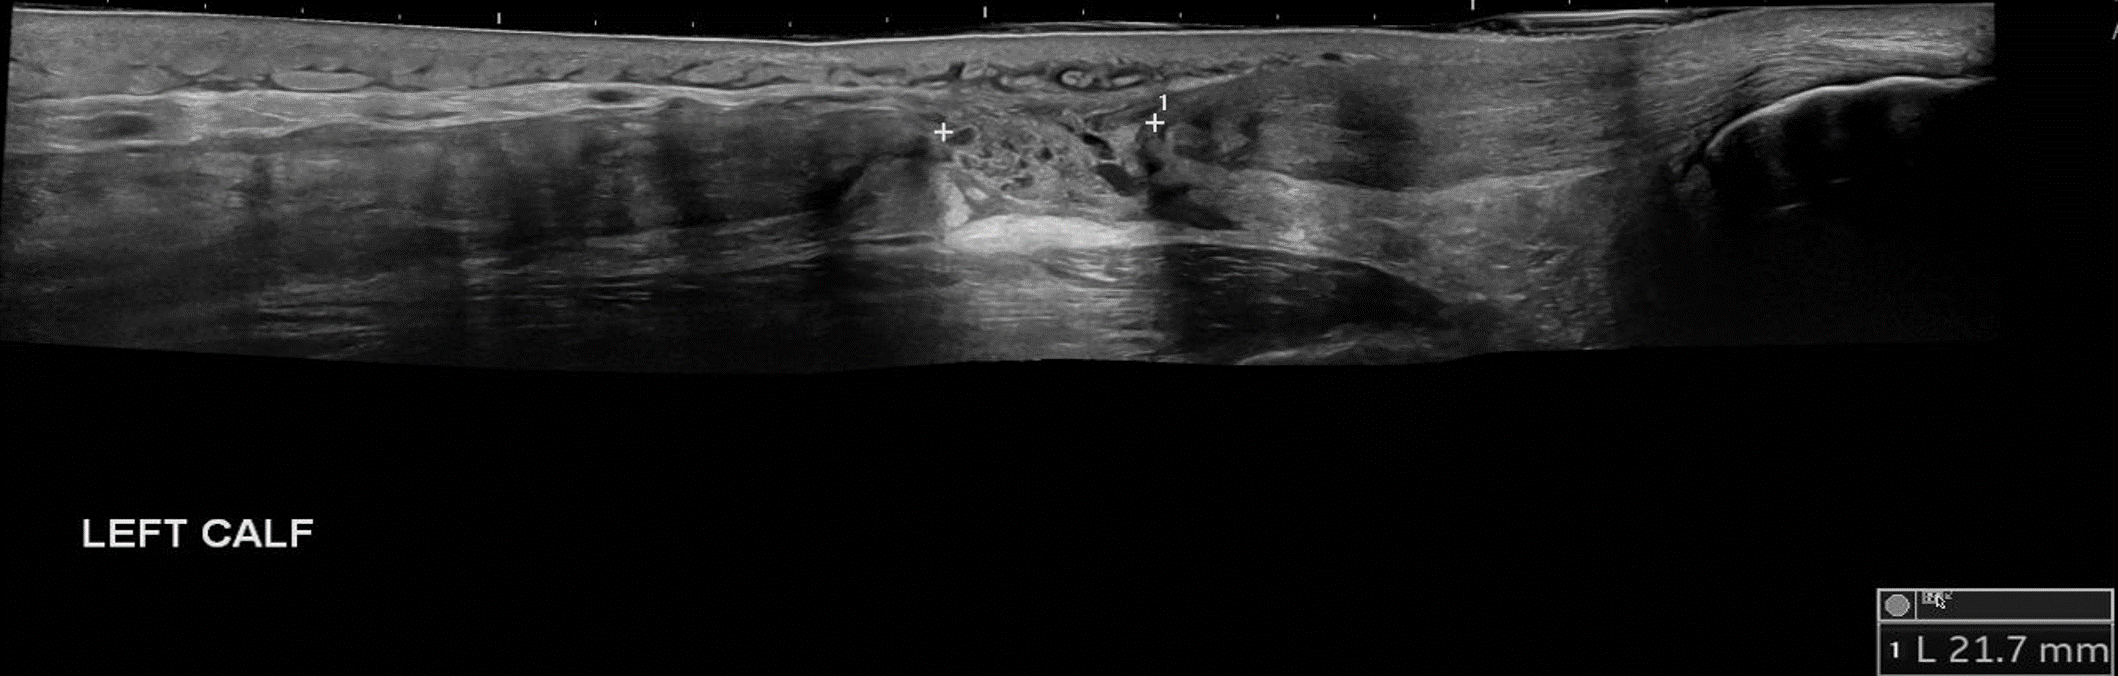

Although classically seen in people who play tennis, it can also be induced by playing squash, skiing, and athletics. Therefore, it typically occurs in active individuals. Extension of the knee and forced dorsiflexion of the ankle seem to be the most frequent biomechanical causes of the injury, which result in rupture of the medial head of the gastrocnemius muscle or injury to the gastrocnemius-soleus aponeurosis, without evidence of muscle rupture.

Ultrasound findings show a hypoechoic linear abnormality (yellow arrows).